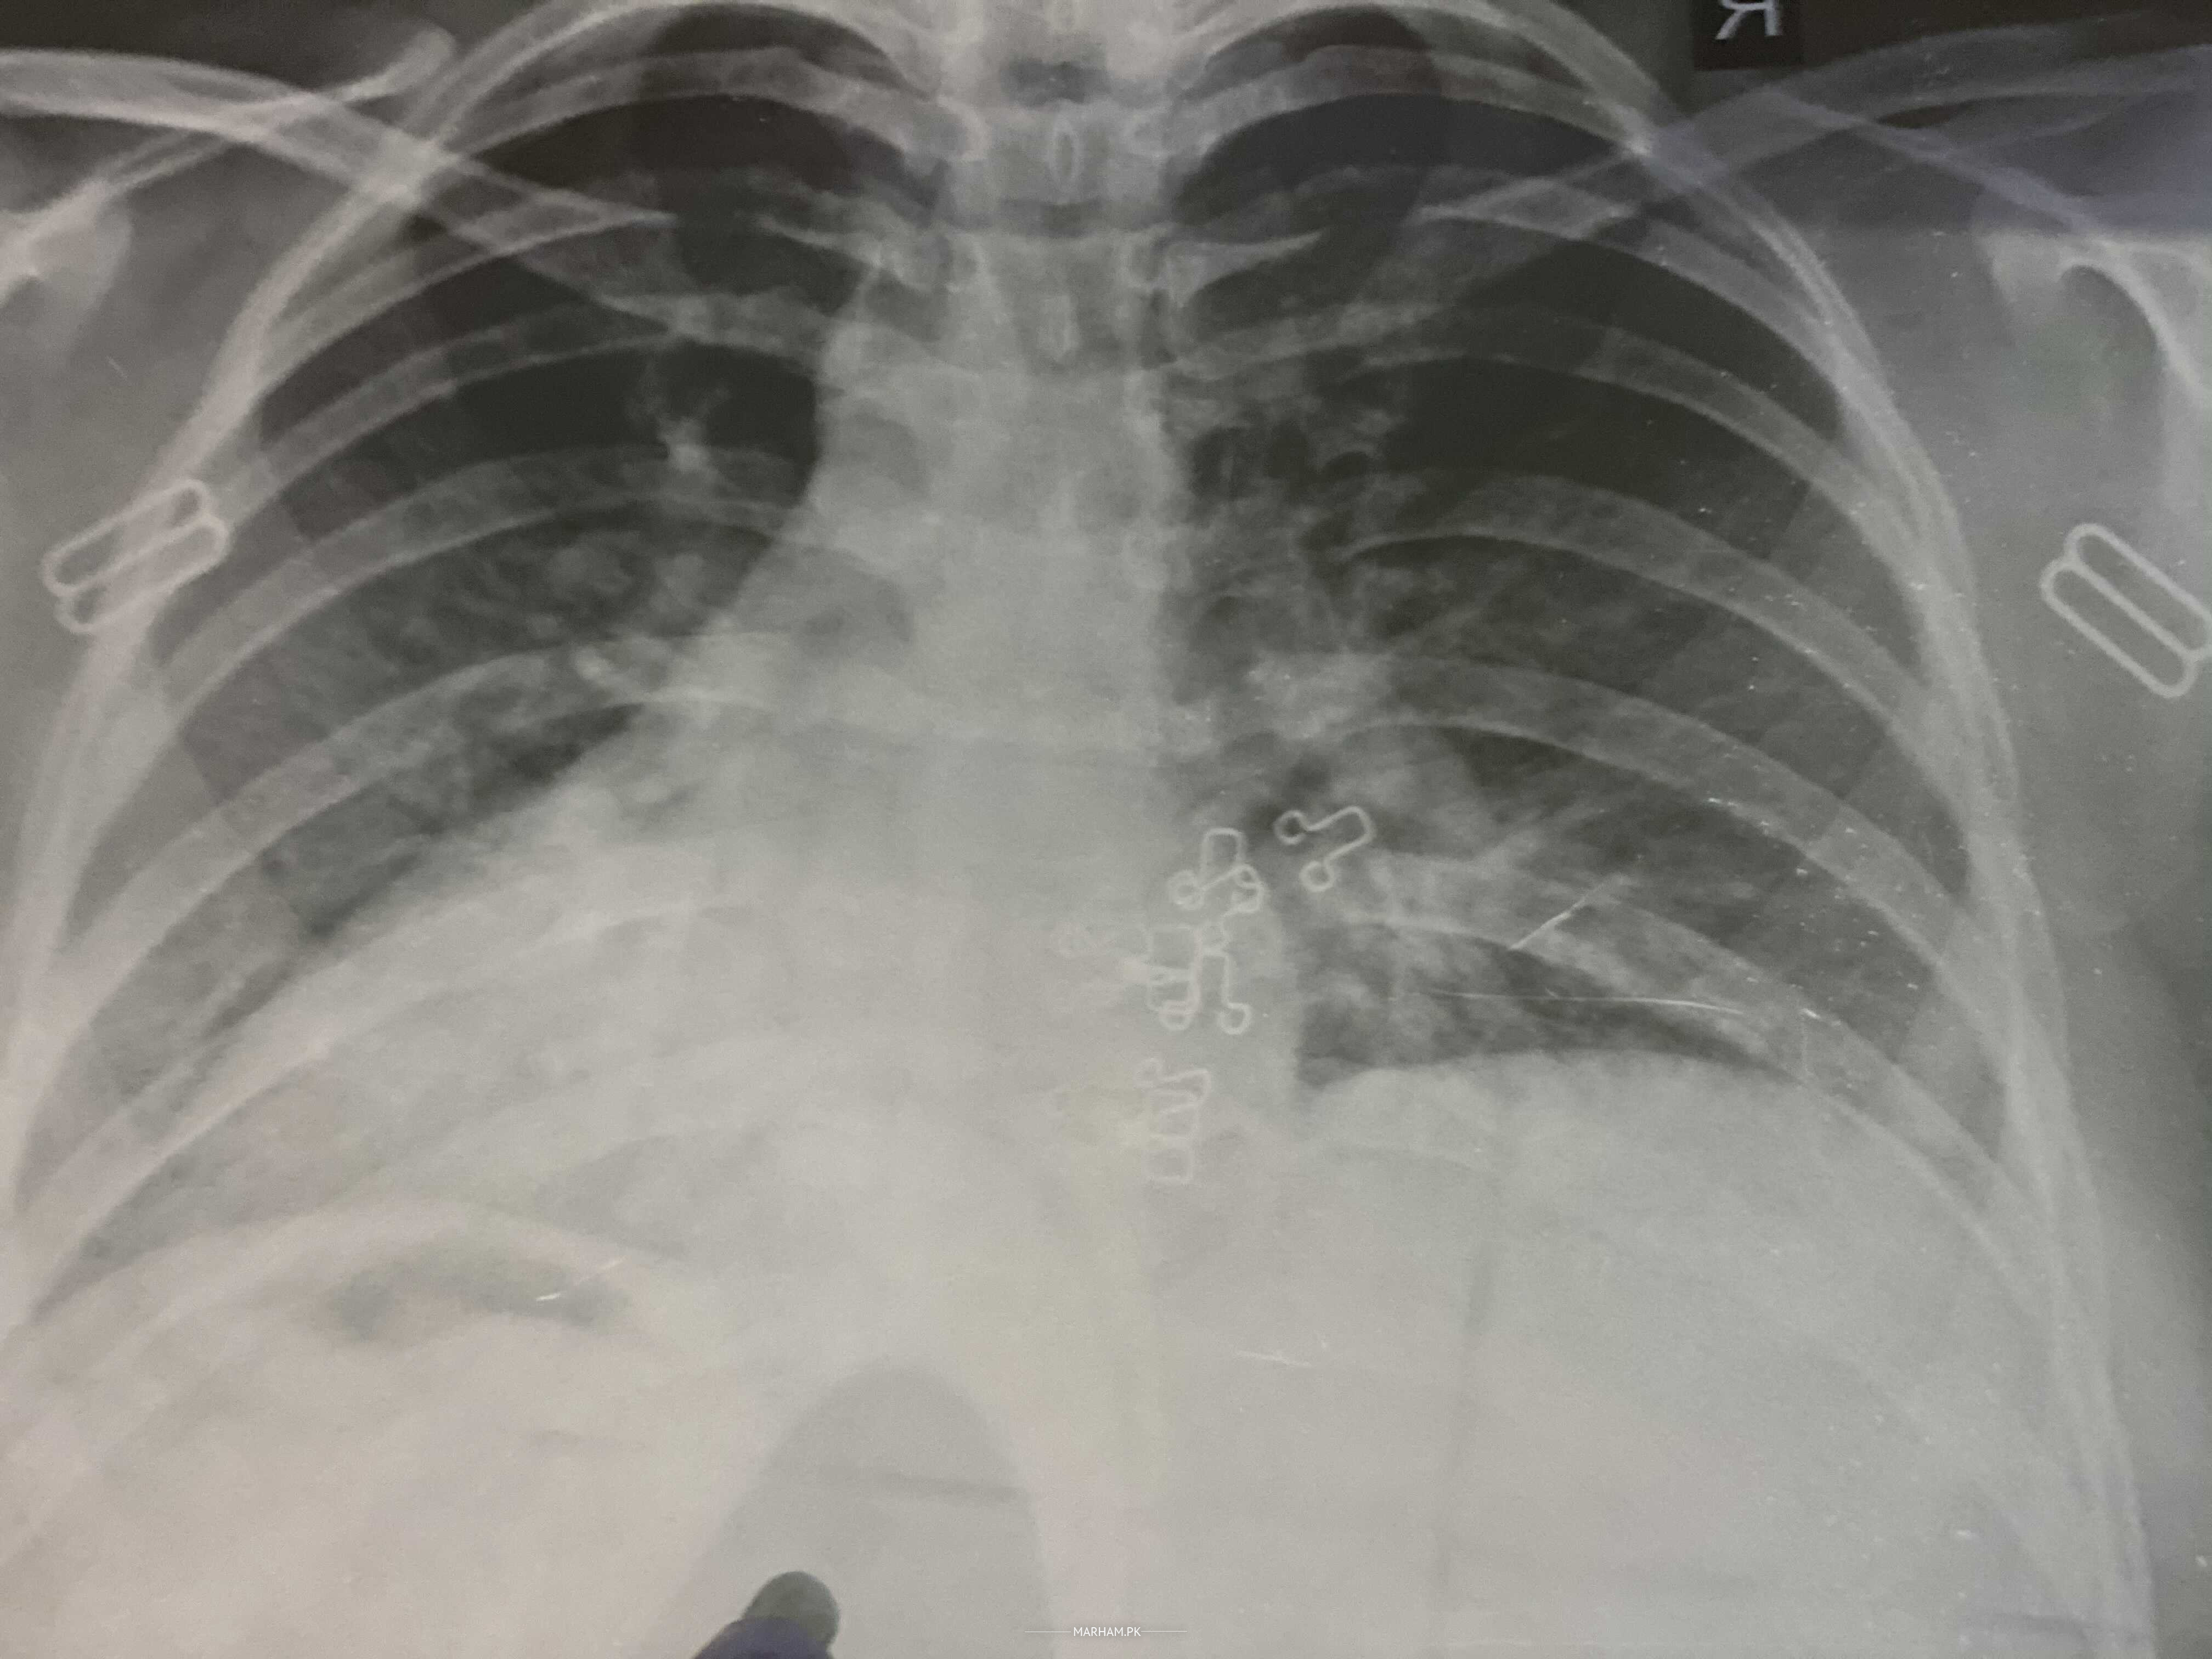

I had sore throat and flu but throat is fine now just halving flu. Kindly tell me about my x-ray is it ok??

cxr seems to be fine can u send more pics that are clear n not rotated.

do covid pcr test,n upload clear non rotated pic of cxr